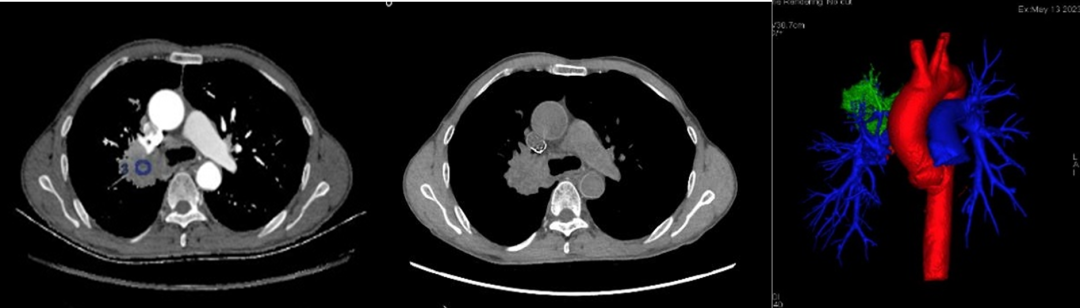

1.單能量圖像:能譜CT可提高圖像質(zhì)量,顯示病灶內(nèi)部特征,臨床可用于所有血管檢查及增強(qiáng)掃描。

2.物質(zhì)定量和分離:實(shí)現(xiàn)定量分析,臨床中常用的碘基物質(zhì)圖像可評(píng)估血管及強(qiáng)化程度。

6.虛擬平掃:在增強(qiáng)掃描圖像基礎(chǔ)上,將除碘化組織外的所有組織均以其原始HU值表示,臨床中可減少患者CT照射次數(shù),降低輻射劑量。